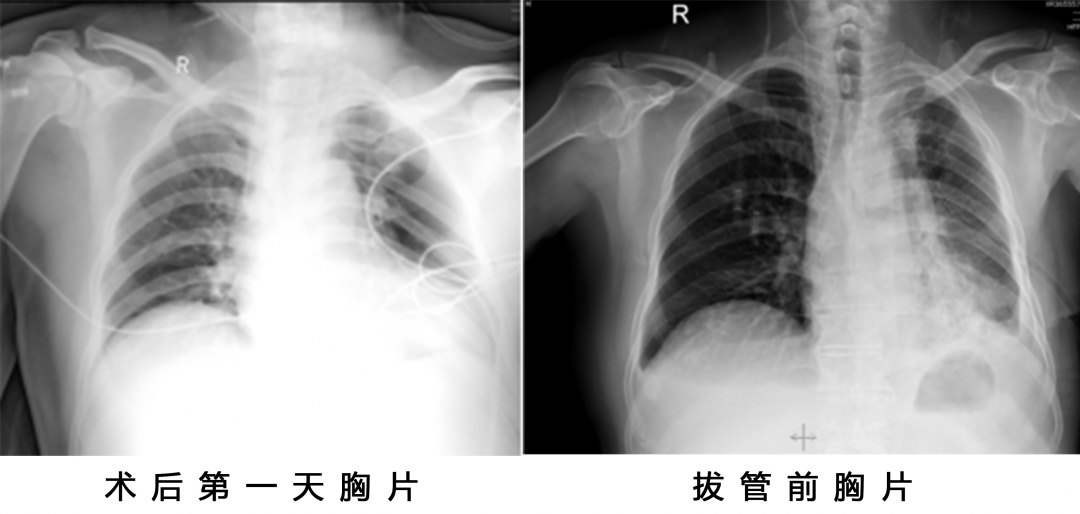

邵主任在多方判断下,病人可以手术切除病灶,术前分期检查也未见明显远处转移。手术方式为全麻单孔胸腔镜下行左上肺叶切除+淋巴结清扫术。

患者进行新辅助化疗后手术难度明显增大,尤其是病灶退缩部位,硬的像钢板,毫无间隙和层次可言,需要医生的耐心和胆量。邵主任从医多年,手术很顺利,历时1.5小时,术中出血仅50ml。

术中见主肺动脉窗淋巴结及肺门淋巴结冻结明显,肺门结构纤维化明显,分离困难,完美避开喉返神经,术后患者也无明显声音嘶哑症状。

术后患者转入病房,第三天拔除胸腔引流管,第四天顺利出院。

术后病理报告:(左肺上叶切除标本):中分化腺癌伴弹力斑块形成(腺泡型约65%,乳头型约30%,微乳头型约5%),肿块大小2.5*2*1.8cm。

支气管切缘(-)。脉管(+)。送检淋巴结(第5、6、7、8、9、10、11、12、13组):均未见癌组织转移。